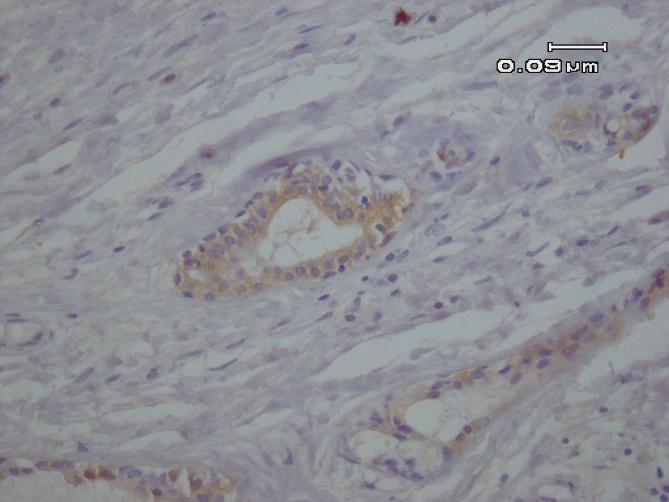

A differential diagnosis including pleomorphic adenoma (PA), clear cell type of mucoepidermoid carcinoma (MEC) and epithelial myoepithelial carcinoma was suggested according to the histological findings. For the definitive diagnosis immunohistochemical (IHC) studies for ki-67, pan-cytokeratin and p63 was performed. The abluminal cells revealed strong immunoreactivity for p63 (Figure 2A), and luminal cells were positive for pan-cytokeratin (Figure 2 B). In addition, Ki-67 proliferative activity was positive in 1% of abluminal cells.

Fig. 2. A. Positive nuclear immunohistochemical expression of p63 in the abluminal cells (IHC, 400X).

In the present study p63 was applied to highlight abluminal myoepithelial cells as it was suggested as the best myoepithelial marker in these tumor in a series of 61 cases (20). CK7 is considered as a marker of ductal luminal cells which is consistent with epithelial

phenotype (21).